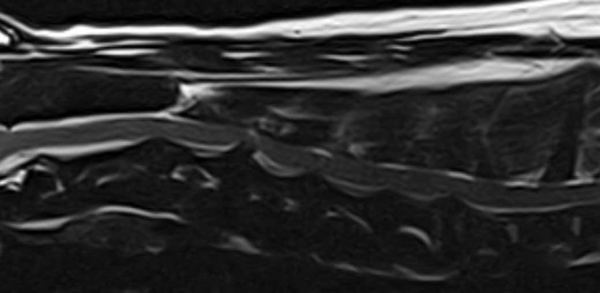

- MRI: Xác định đĩa đệm C3 – C4 thoát vị, chèn ép tủy sống cổ, gây triệu chứng thần kinh.

MRI xác nhận thoát vị đĩa đệm C3 – C4 ra phía sau, biến dạng tủy sống, có tín hiệu T2W cao quanh vùng chèn ép.

Các đĩa đệm cổ khác cũng xuất hiện dấu hiệu mất nước ở nhiều mức độ.